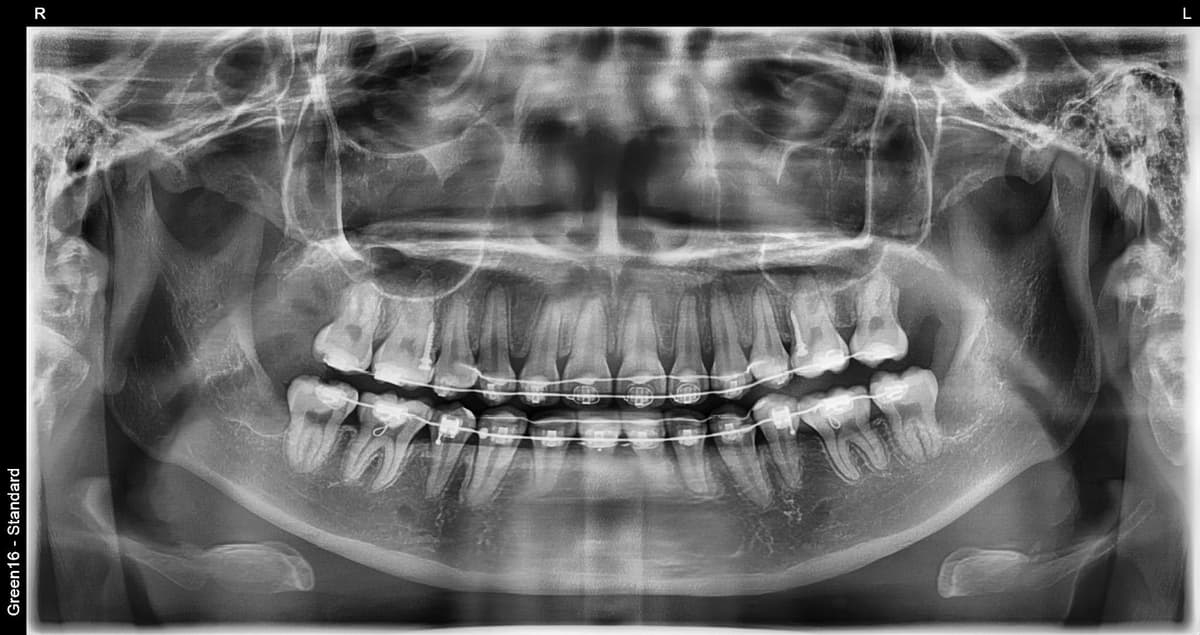

RISK LEVELS

Aql tishi holatiga qarab xavf darajasi

After

Past xavf

Oddiy aql tishi

Normal o'sgan aql tishi ham parvarish qilish qiyin bo'lgani uchun karies xavfi yuqori

O'rta xavf

Qisman ko'milgan aql tishi

Ovqat qoldiqlari yig'ilib qolishi oson va yallig'lanish tez-tez yuzaga keladi

Yuqori xavf

To'liq ko'milgan aql tishi

Kista hosil bo'lishi mumkin bo'lgani uchun erta sug'urib olish kerak

Ortodontiya davrida aql tishi

Ortodontiya davolash jarayonida aql tishini sug'urib olish zarur bo'lgan holat